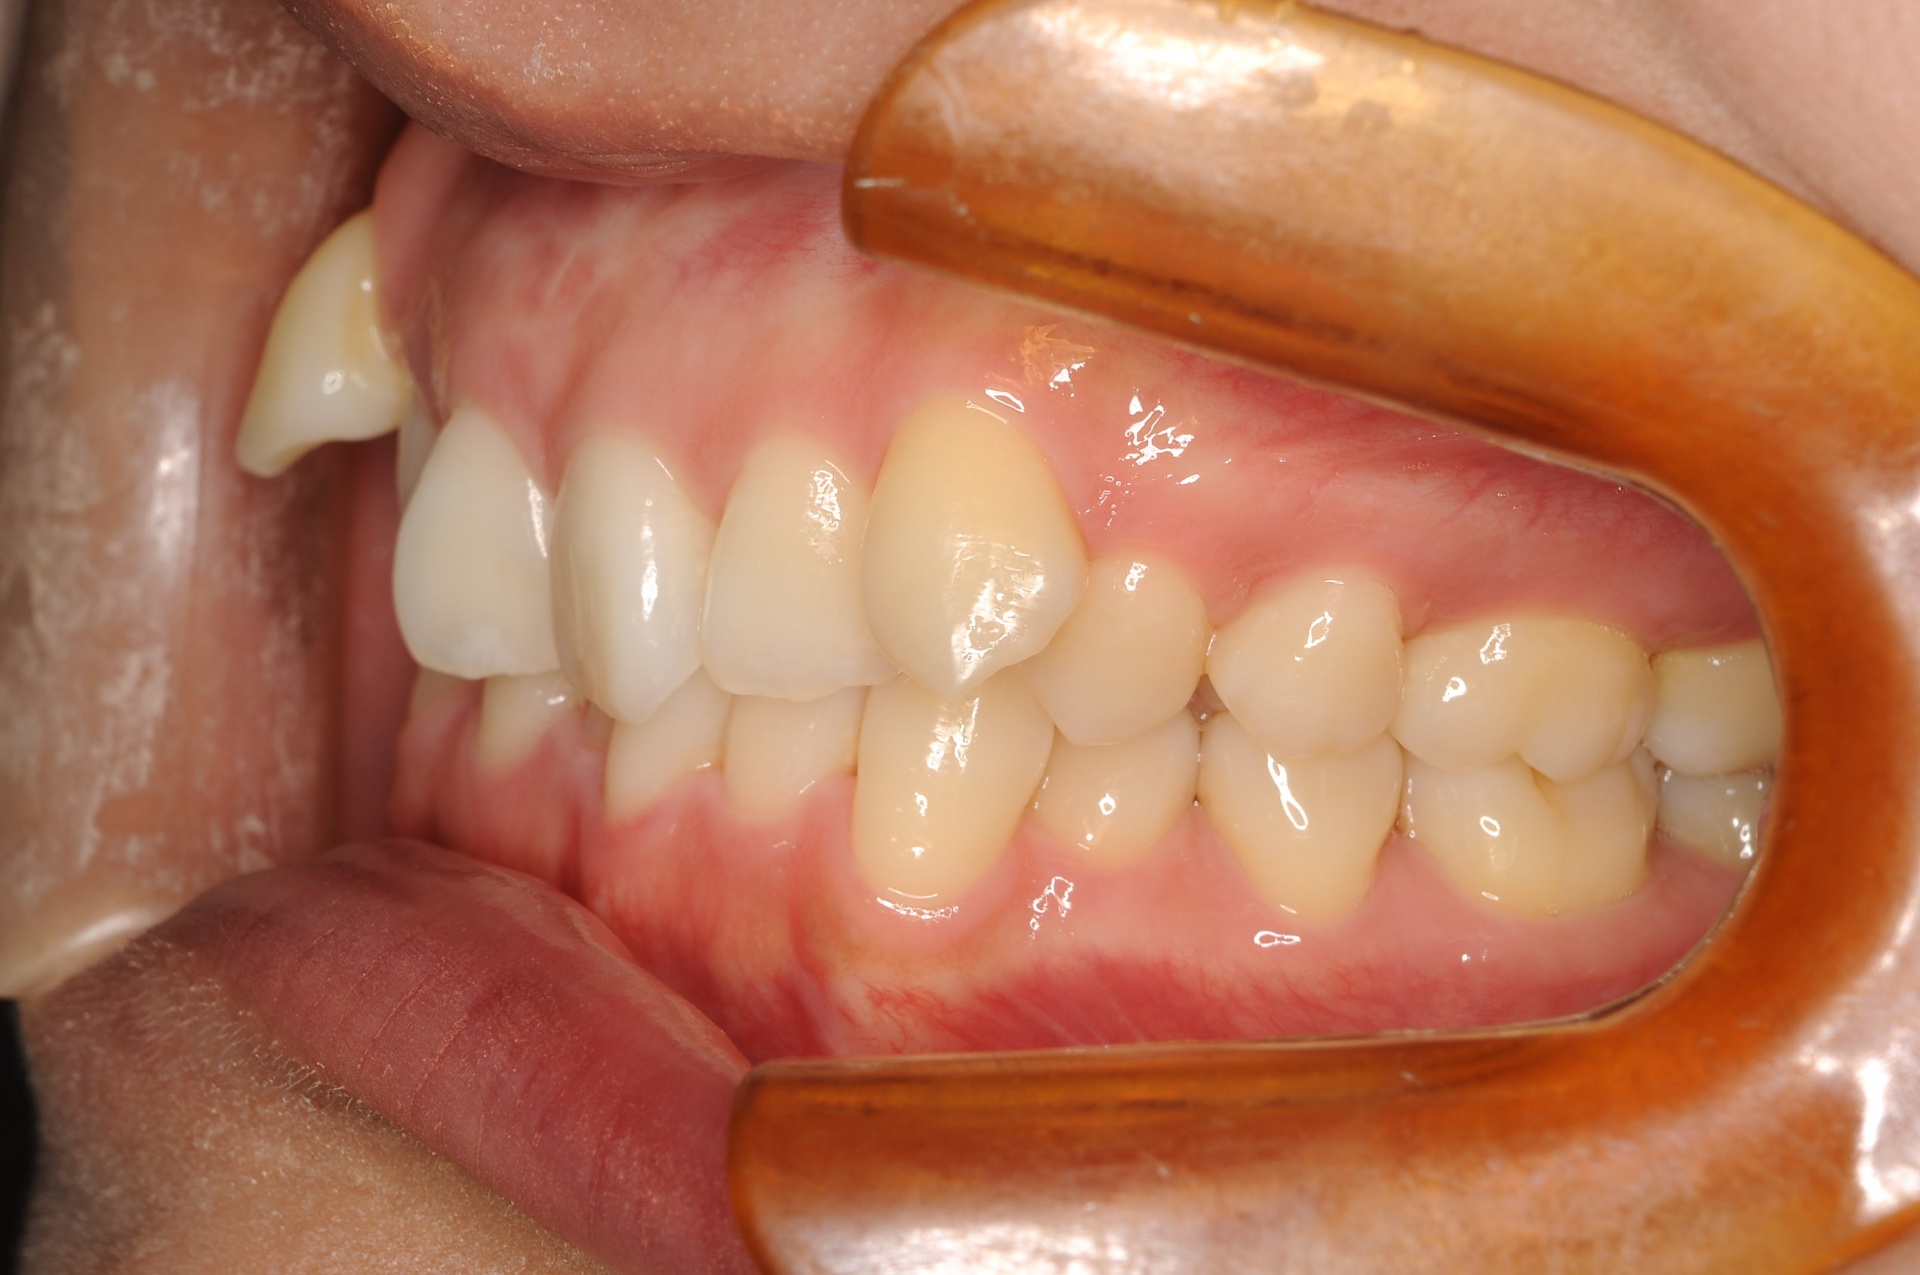

治療中

見えない装置(裏側矯正)を希望されましたので、上顎は裏側に装置をつけて、下顎はセラミックの白い装置としました。上顎両側犬歯を小臼歯の抜歯したスペースへ移動させました。下顎は非抜歯で叢生を改善しました。